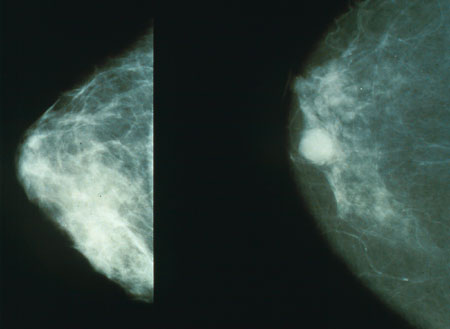

Mamografias mostrando uma mama normal (esquerda) e uma mama com câncer (direita). Crédito: Domínio Público